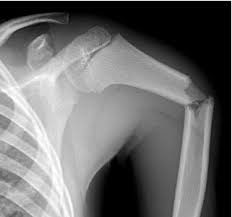

שבירת עצם הבריח - קלויקולה